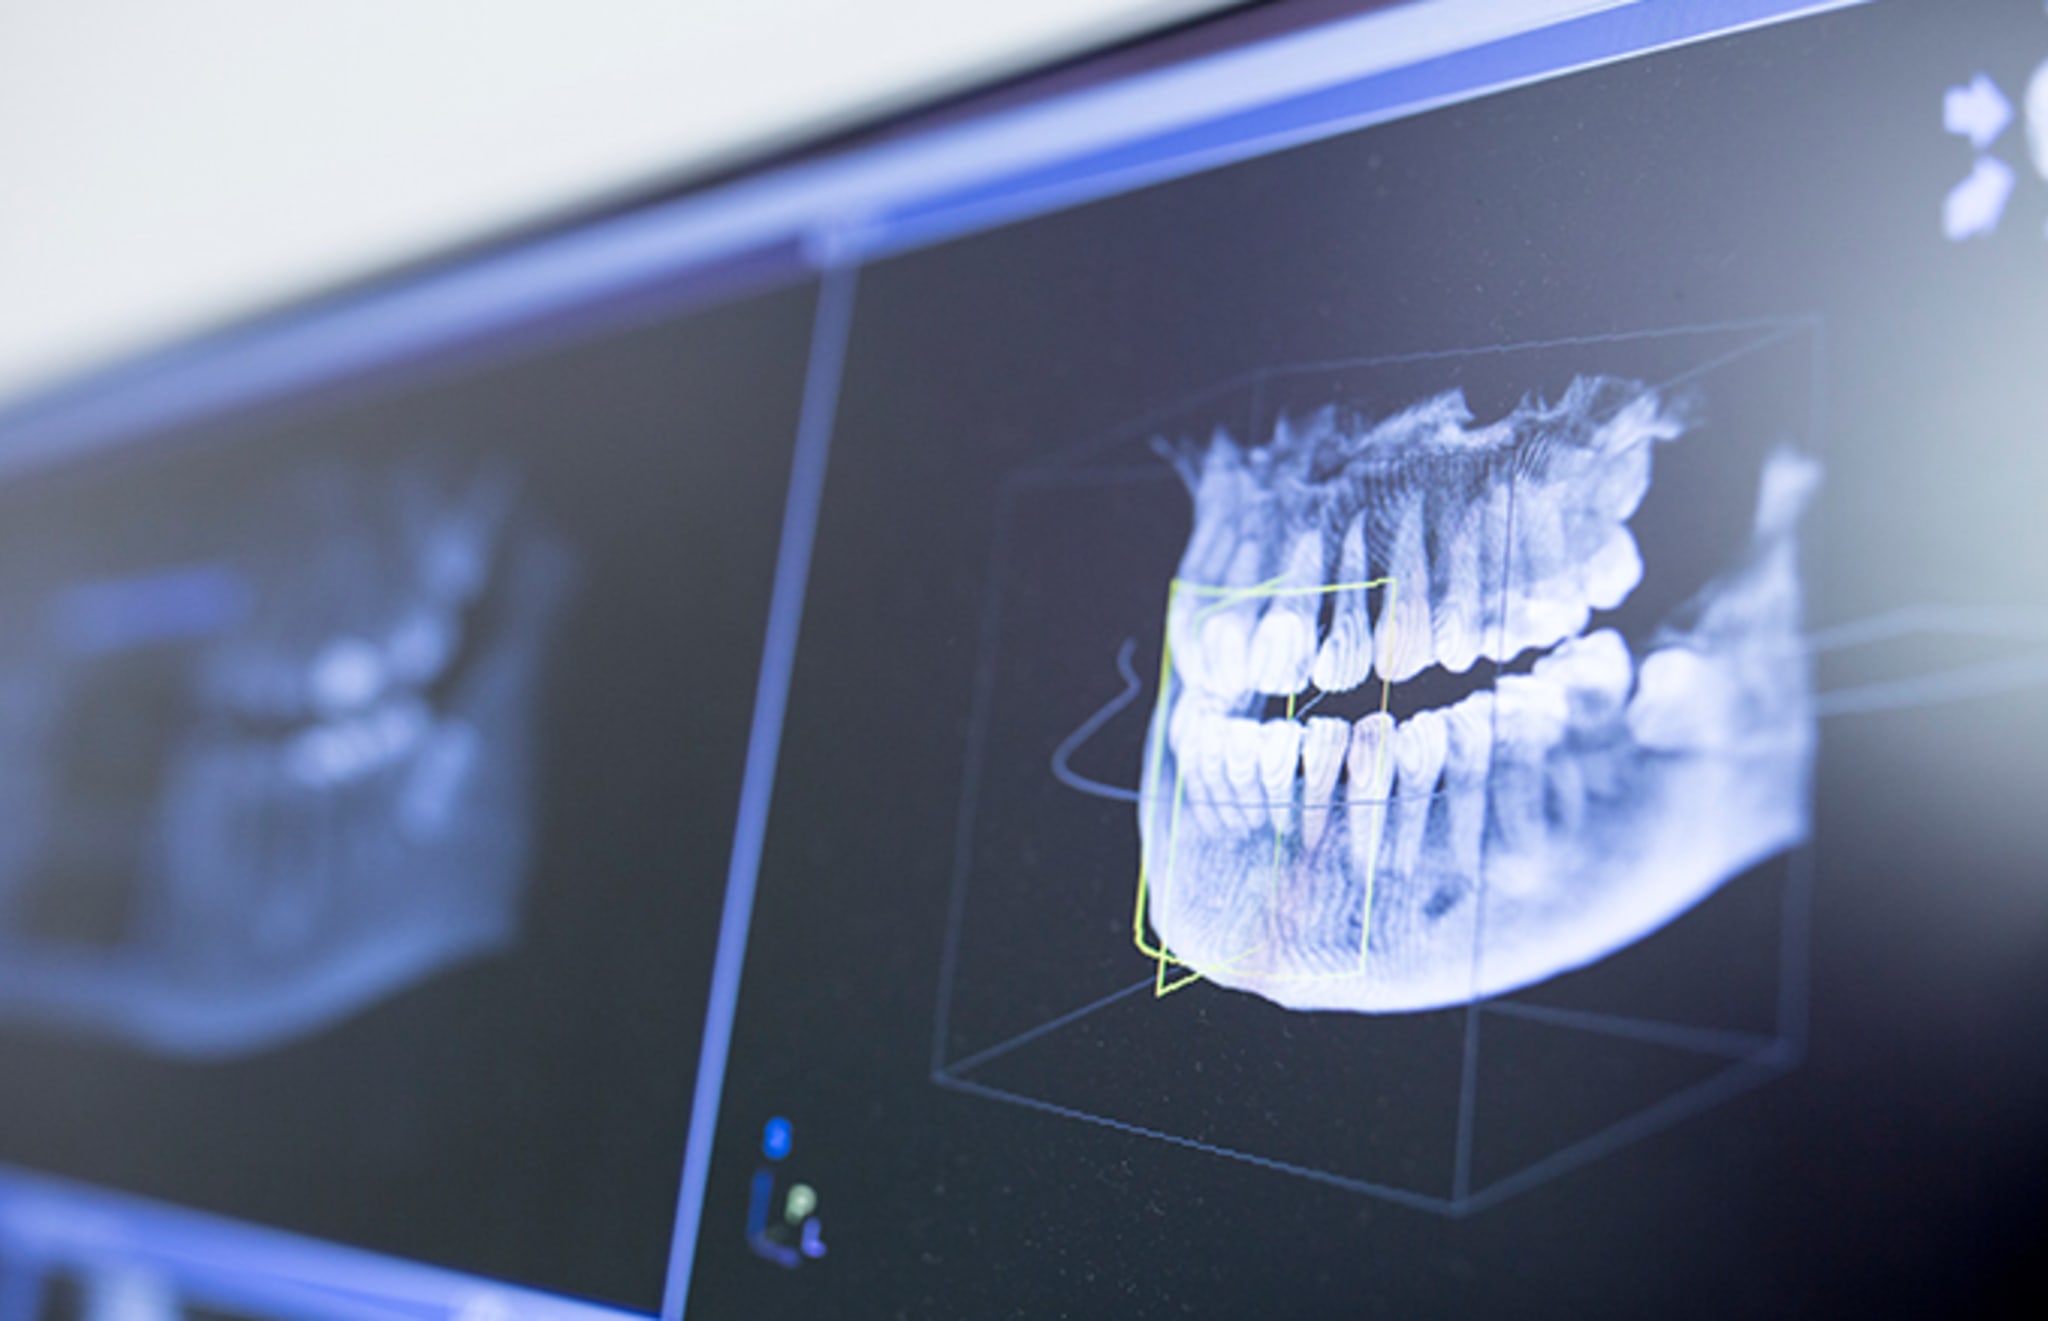

A seven-year-old boy in India complained about severe jaw pain, and when he was taken to the hospital it was revealed to him that he had 526 teeth in his mouth. As CNN reports, the boy was taken to a hospital in Chennai, due to swelling and jaw pain. When he was given an x-ray by doctors at the hospital, it was discovered that the boy had a sac embedded in his jaw filled with a huge amount of teeth.

Dr. Prathiba Ramani explained that the surgery to remove the teeth from his mouth took place last month, but she and her team still had to closely inspect each tooth. Two surgeons operated on the boy and removed the sac from his month, which prompted hours of emptying the teeth from the sac. "There were a total of 526 teeth ranging from 0.1 millimeters (.004 inches) to 15 millimeters (0.6 inches). Even the smallest piece had a crown, root and enamel coat indicating it was a tooth," she explained.